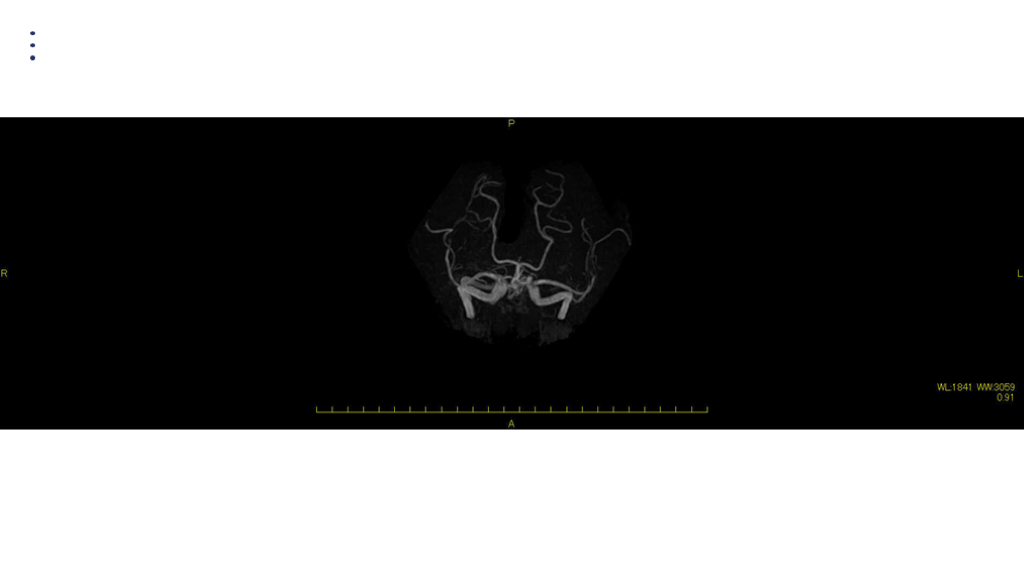

画像 所見 DAY 14 MRA 悪化